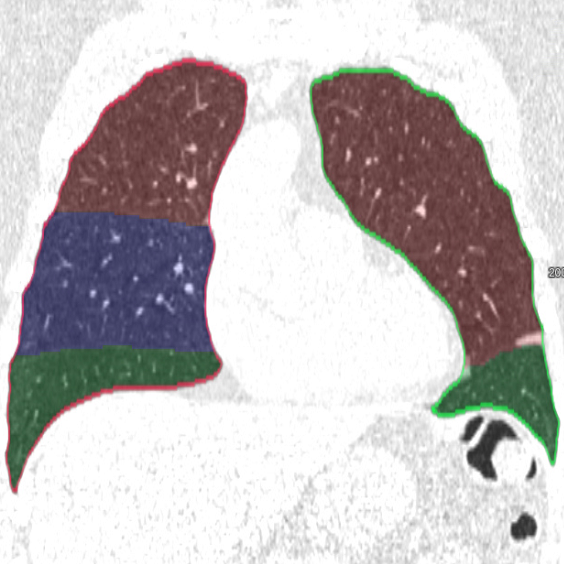

Training: We train two separate 3D u-nets (see Figure LABEL:fig:method), one for the left lung with 3 labels (background, upper lobe, lower lobe) and one for the right lung with 4 labels (background, upper lobe, middle lobe, lower lobe). We use 4 resolution levels, a filter size of for the convolutions, PReLu activation, batch normalization and dropout.

Inference: For segmentation, we first resample a CT scan to 1.5 . Next, we apply our trained networks for the left and the right lung lobes and upsample the image back to the original resolution. We propose the following postprocessing to deal with remaining misclassifications regions (see Figure LABEL:fig:method): We perform a connected component analysis and keep the largest two (three) components in the left (right) lung. Finally, we fill the holes with a Voronoi division and use a given lung mask to delete all objects outside the lungs.

We applied the described segmentation pipeline to the 14 testing datasets which were not used for training and validation. Segmentation including postprocessing takes less than 6 seconds for a case. We compared our method to two other approaches: 1. a non-deep-learning-based automatic method [Lassen et al.(2013)Lassen, van Rikxoort, Schmidt, Kerkstra, van Ginneken, and Kuhnigk] 2. the same u-net as proposed but without weighting. The mean distance from the visible fissure improved to 1.46 mm (without weighting: 2.08 mm). See Figure 2 for plots and Figure 3 for screenshots.

We trained a 3D u-net for a lung lobe segmentation task and showed that emphasizing the lobar boundaries in the loss function improved the segmentation results (see Figure 2 and 3). The segmentation quality is comparable to the method proposed in [Lassen et al.(2013)Lassen, van Rikxoort, Schmidt, Kerkstra, van Ginneken, and Kuhnigk] and even slightly better for the left lobes. This study was performed on a small amount of data. In future work, we plan to train with the same architecture on a much larger database including a wide range of pathologies and performing an extensive evaluation with participation in the LOLA11 [LOLA11()] challenge.